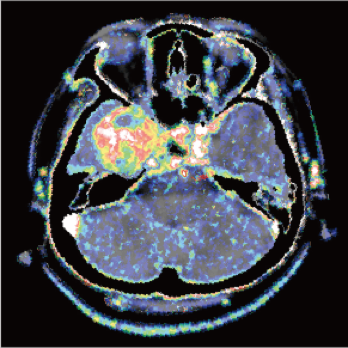

3 core components built on a new industry-leading configuration

Large-capacity tube delivers exceptional stability and durability, ensuring consistently high-quality output even under heavy workloads

High-power generator delivers high mA output for rapid scanning of complex anatomy and large coverage areas, boosting scan speed while enhancing image signal-to-noise ratio and minimizing artifacts

Wide detector expands single-rotation coverage, shortens exam time, reduces motion artifacts, decreases radiation dose, and saves tube exposure time while effectively lowering operating costs